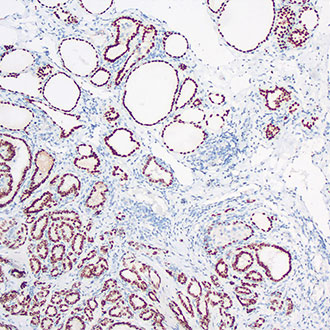

CK19

CK19 -